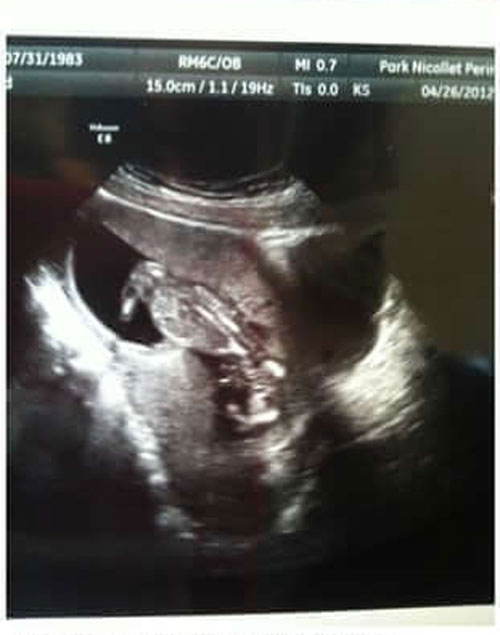

ಇಂಡಿಯಾನಾ ದೇಶದ ಓರ್ವ ತಾಯಿಯು ತನ್ನ ಅಲ್ಟ್ರಾಸೌಂಡ್ ಸ್ಕ್ಯಾನ್ ಫೋಟೋವನ್ನ ನೋಡಿ ಖುಷಿ ಪಟ್ಟು ಸುಮ್ಮನಾದಳು. ಆದರೆ ಆಕೆಯ ಸ್ನೇಹಿತೆ ಹೇಳಿದ ಮೇಲೆಯೇ ಗೊತ್ತಾಗಿದ್ದು, ಆ ಫೋಟೋದಲ್ಲಿ ಯೇಸು ಕ್ರಿಸ್ತನನ್ನು ಶಿಲುಬೆಗೆ ಏರಿಸಿರುವುದನ್ನ ಕಾಣಬಹುದು ಎಂದು. ಈಗ ಕಣ್ಣಮುಂದೆ ಅದೇ ಬರುತ್ತದೆ !